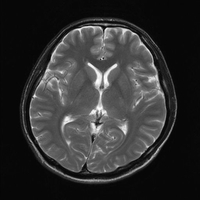

パンチドランカー(2)「打ち合い」は素人でもできる、「もらわない技術」こそ修練の証。

「脳を守る」意識こそ、一流選手と二流以下の選手の「見えない差」 ーーーーーーーーーーーーーーーーーーーーーーーーーーーーーーーーーーーーーー ・予防の意識が低い指導者に注意! ・脳への衝撃を減らす練習体系とは? ・「打ち合い」は素人でもできる。「もらわない技術」こそ修練の証。 ・シャドーは選手の身分証明…